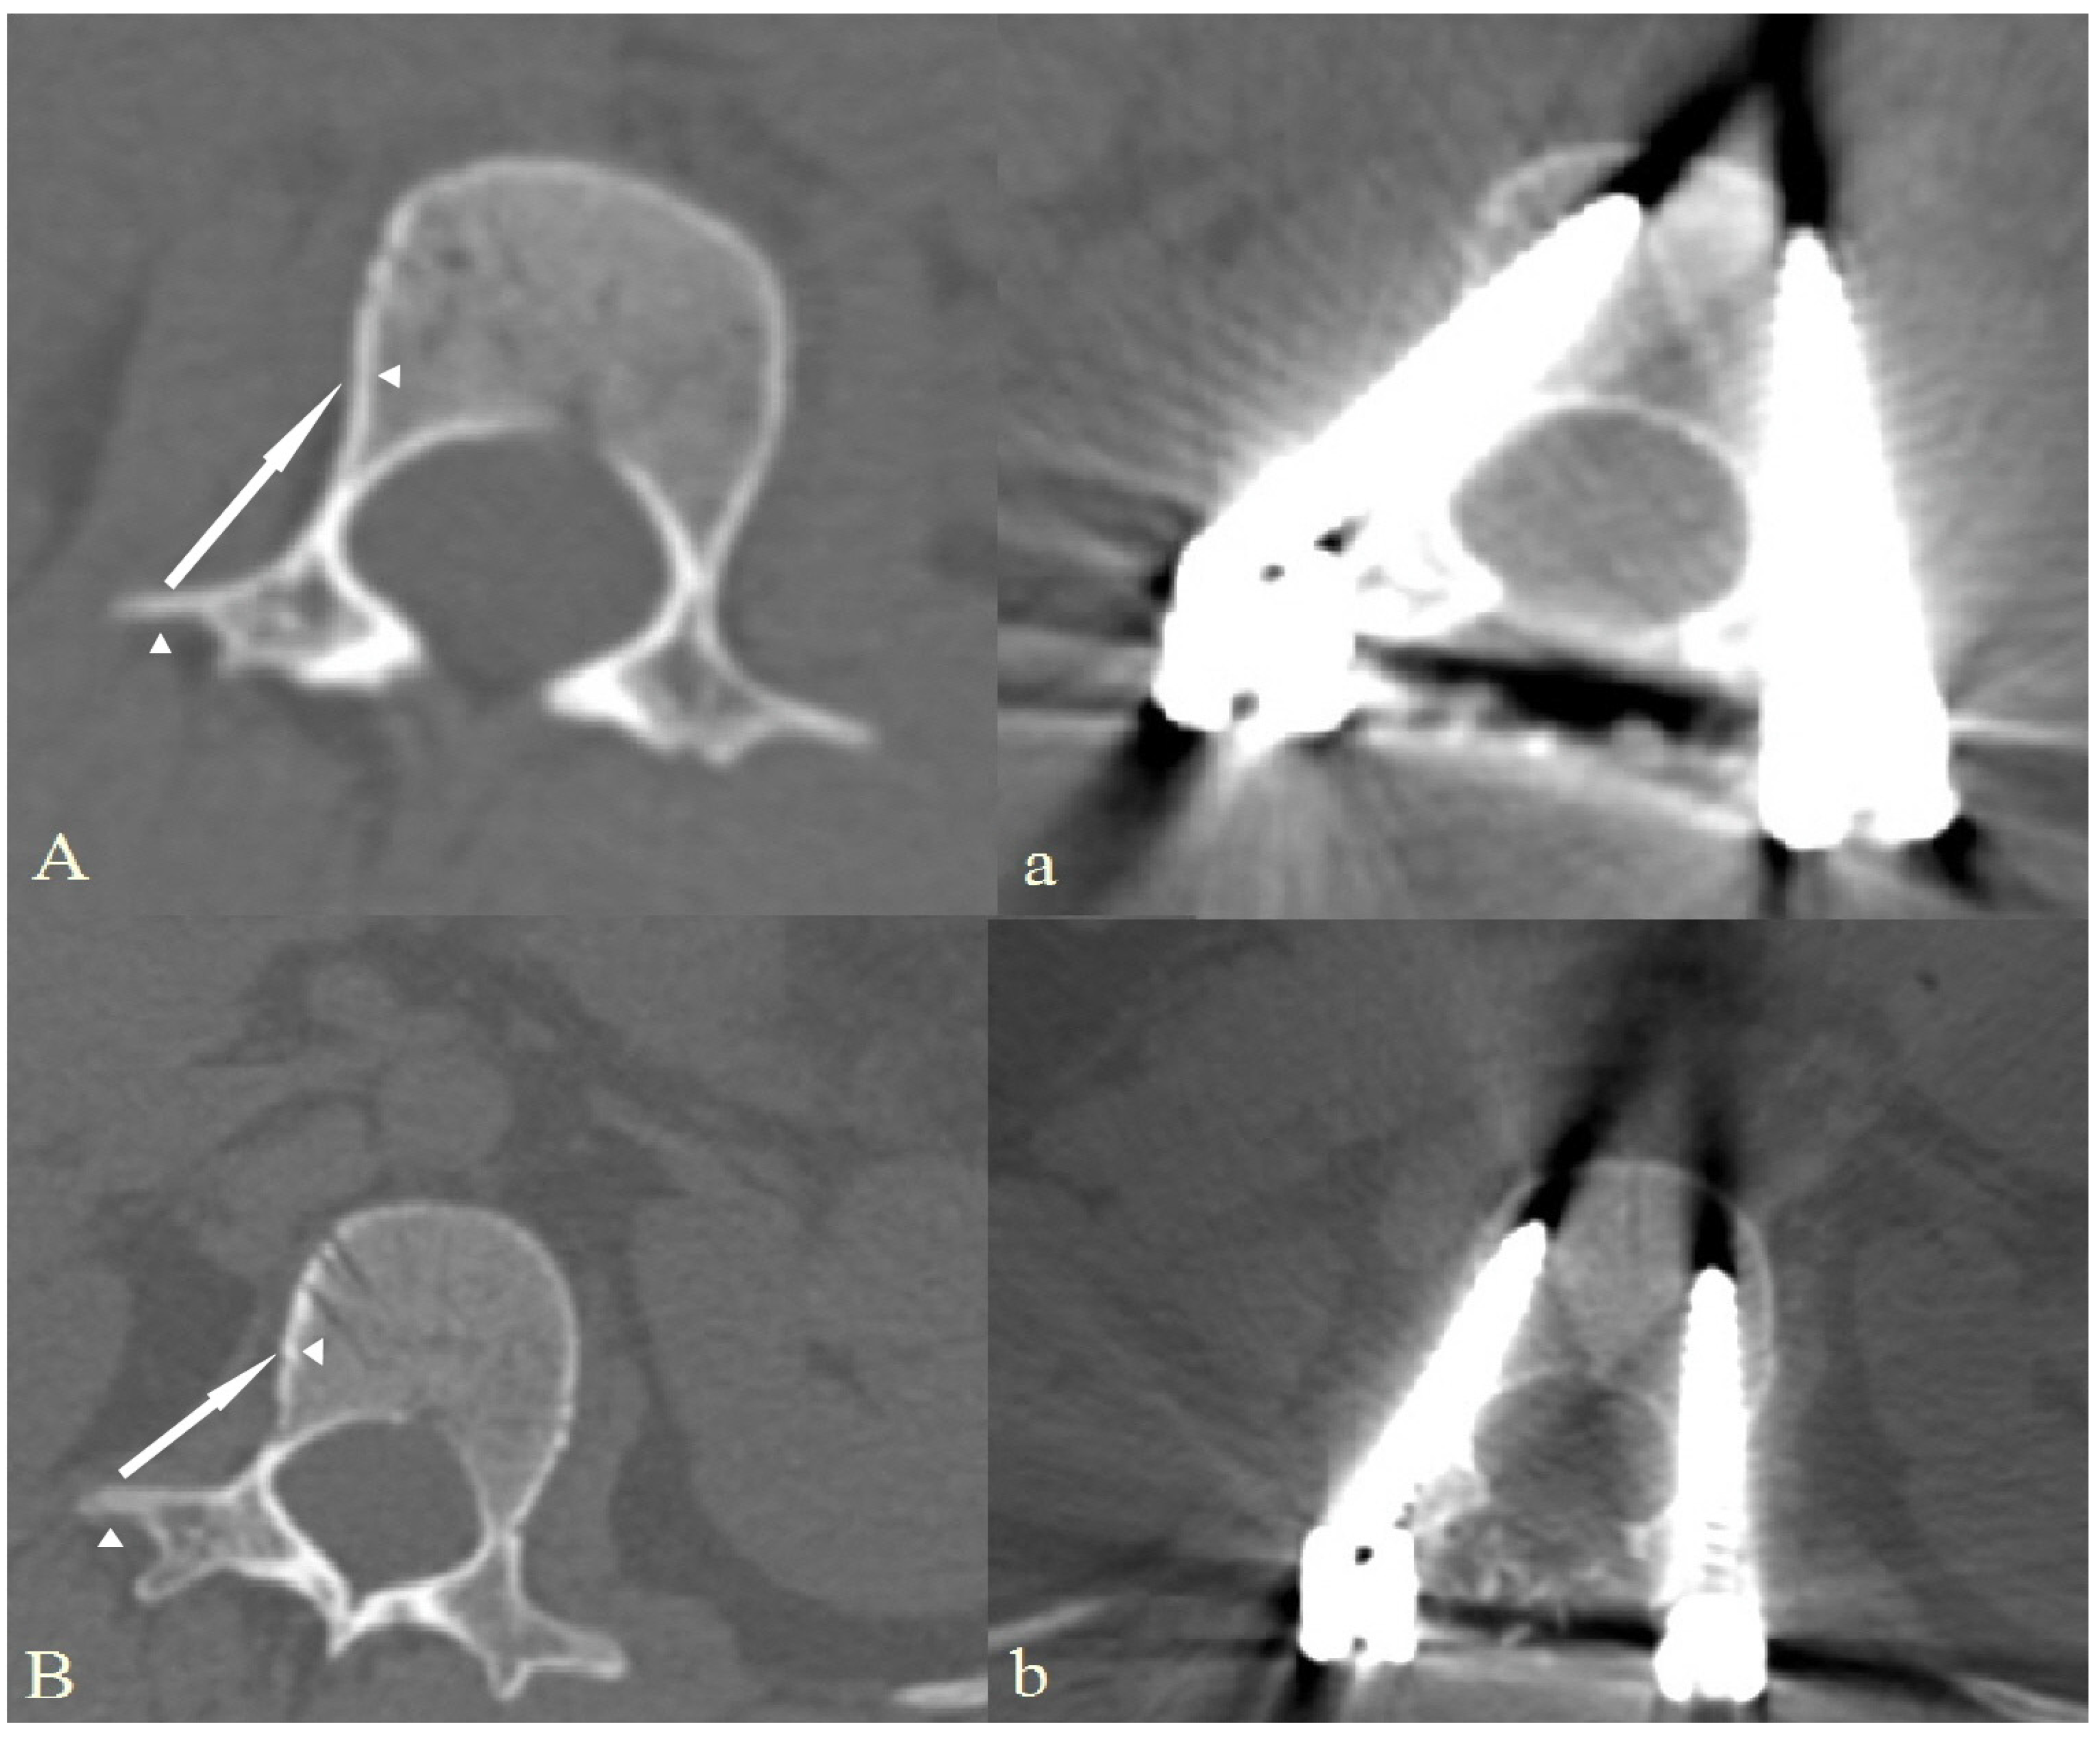

2.3. Surgical Technique